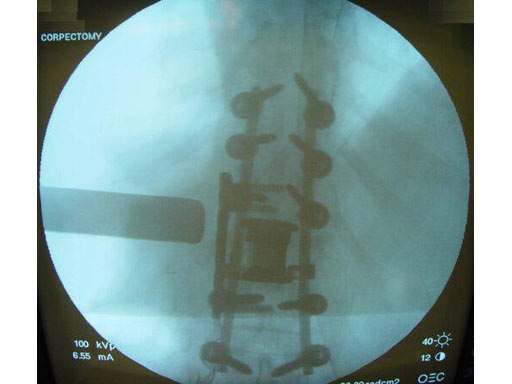

Pathology: 68 - year- old male sustained a high energy C-type shear fracture of the L1 vertebra after a fall off of a bridge. The patient had received posterior fixation three weeks before this accident, but still displayed intractable leg pain. The posterior fixation consisted of Dual - Opening USS pedicle screws at T10 -T12 and L2- L3. The preoperative x- rays and MRI showed that the patient had some slippage at the L1- L2 disc and that there were still several pieces of bone impinging on the spinal canal.

Indication: Corpectomy of the L1 vertebral body.